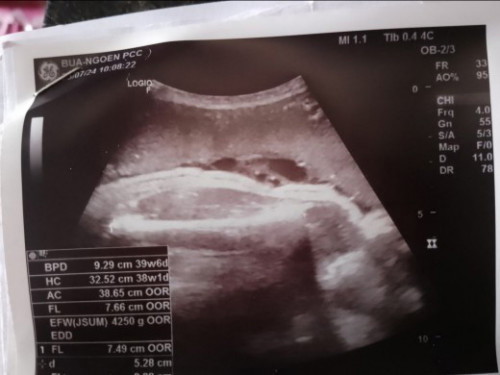

ท้องได้37วิกน้องหนัก4250กรัม แม่ๆบ้านไหนน้ำหนักน้องเยอะเหมือนบ้านนี้ไม่ค่ะ